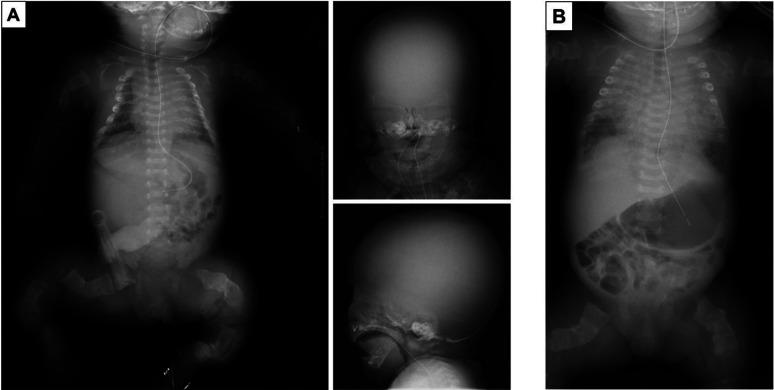

我们报告了一例成骨不全症(OI)患者,尽管呼吸状况相对稳定,但在服用帕米膦酸钠(PA)4 d 后出现肺出血。引入双膦酸盐是为了降低破骨细胞的活性,目前已广泛用于 OI 患者。双膦酸盐在儿童中的耐受性通常很好,治疗标准包括周期性静脉注射 PA。但实际上,在新生儿期使用 PA 治疗严重 OI 的经验有限,其安全性仍不确定。本报告旨在描述一名新生儿 2 型 OI 患者可能与 PA 相关的呼吸系统事件,提示使用 PA 后可能会出现肺出血等危及生命的严重并发症。需要进一步研究评估肺出血与使用 PA 之间的关系,以加强预防措施。

We report the case of a patient with osteogenesis imperfecta (OI) who developed pulmonary hemorrhage 4 d after pamidronate disodium (PA) administration, despite a relatively stable respiratory status. Bisphosphonates are introduced to reduce osteoclast activity and are now widely used in patients with OI. Bisphosphonates are typically well-tolerated in children, and the standard of care involves cyclic intravenous administration of PA. However, in practice, there is limited experience with the use of PA for severe OI during the neonatal period, and its safety remains uncertain. This report aimed to describe the respiratory events potentially associated with PA in a neonatal patient with OI type 2, suggesting that serious life-threatening complications of pulmonary hemorrhage may occur after PA administration. Further studies are required to assess the relationship between pulmonary hemorrhage and PA administration, aiming to enhance prophylaxis measures.